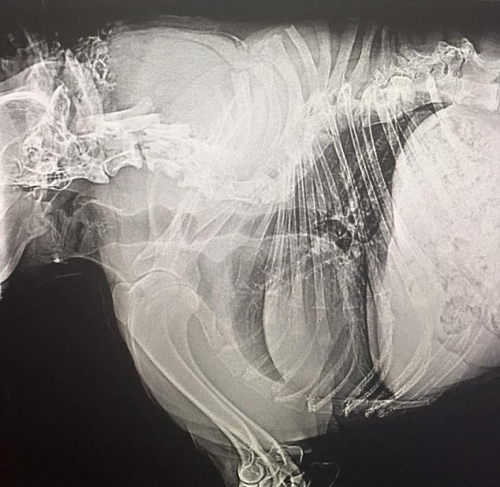

据悉,卡西莫多之所以没有脖子是因为罹患了一种叫“短脊椎综合症”的病。目前,全世界仅有15例。

动物保护中心在对卡西莫多检查后还发现,它颈椎的部分全挤在一块,因此为了避免对其的肺部及其他器官造成压力,卡西莫多每一餐的量必须要有所控制。